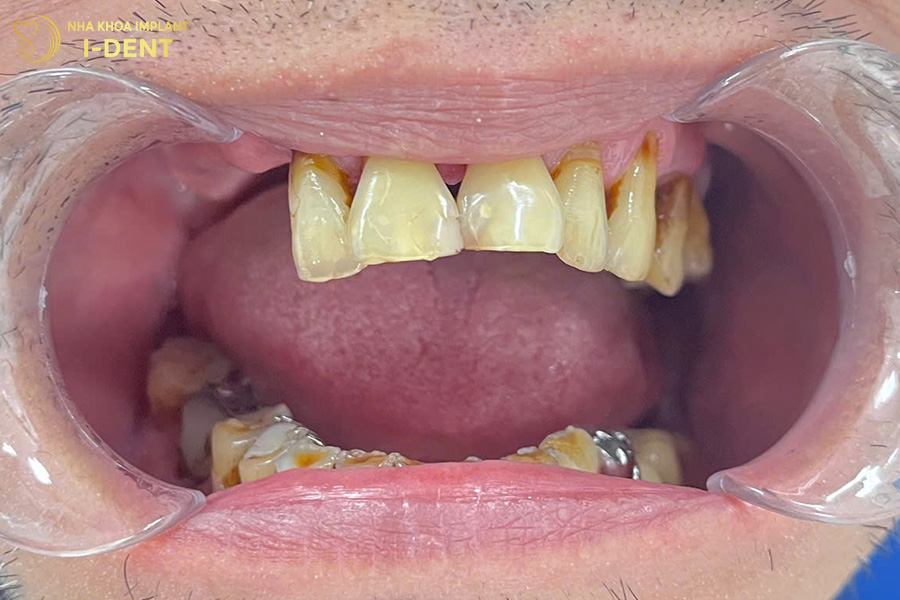

Tình trạng răng ban đầu của chú Trương Văn Sự

Nhận định đây là một tình trạng bệnh khá phức tạp, bác sĩ Đình Tín đã thăm khám kỹ lưỡng và đưa ra kế hoạch điều trị chi tiết. Đầu tiên, bác sĩ Tín chỉ định nhổ các răng lung lay, phẫu thuật ghép xương lớn tại những vị trí tiêu xương, sau đó mới tiến hành cấy ghép Implant toàn hàm All-on-4 cho chú Sự. Cuối cùng là phục hình toàn hàm với răng sứ Chrom-Cobalt (Mỹ) trên Implant cho chú.

Hình ảnh răng chú Sự sau khi cấy ghép Implant All on 4 cho hàm trên